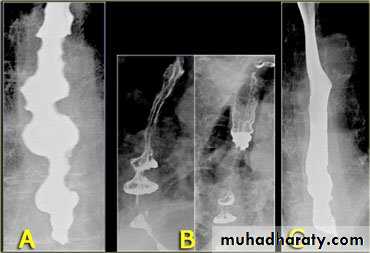

On the far left a traction diverticulum (arrow) due to hilar granulomatous disease. Calcified adenopathy (asterisk). In the middle a pulsion diverticulum (arrow) due to high intra luminal pressure.On the right multiple pulsion diverticula (arrows)

1-Dilatation of venous plexus in the wall of the esophagus due to increased pressure ( portal H.T.).

2-Important cause of Hematemesis .

3-Early changes seen in the mucosa (D.C.) loss of parallelism with thick and tortuous folds.

4-Later multiple small filling defects (fine cobble stone).

5-In advanced stage large filling defects ( coarse cobble stone ) .

6- More advanced stage elongated and worm like filling defect .

7-The changes are seen at lower third and gastric fundus.

Esophageal Varieces